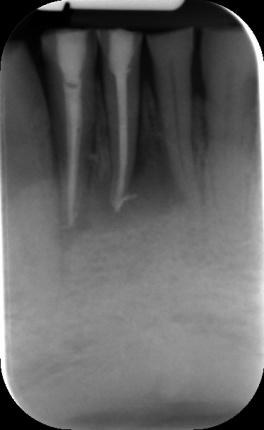

Endodontické ošetření znamená ošetření vnitřního prostoru zubu. Často je nazýváno jako čištění kanálků nebo vytahování nervů. Při endodontickém ošetření ale nejde jen o to „umrtvit zub“ a vyčistit kanálky. Aby bylo endodontické ošetření úspěšné, je třeba kořenové kanálky ošetřovaného zubu nejen vyčistit, ale i rozšířit, vydezinfikovat a zaplnit materiálem, který kořenové kanálky dokonale utěsní.

Endodontické ošetření je nutné provést vždy, když dojde v zubní dřeni k patologickému procesu – zánětu nebo jejímu odumření. Zánět zubní dřeně je většinou způsoben bakteriemi (infekcí), které do dřeňové dutiny pronikly ze zubního kazu. Zubní dřeň může také onemocnět při úrazu zubu (pohmoždění zubu, zlomenina zubu).

Zánět vede k rozpadu zubní dřeně a k postupnému proniknutí infekce do celého kořenového systému. Bakterie se kořenovým kanálkem dostávají do těsné blízkosti nebo přímo do čelistní kosti. Na tento stav reaguje imunitní systém rozvojem zánětu kolem kořene zubu a vzniká tzv.“ zubní váček“. Náš imunitní systém bohužel nedokáže odstranit infekci uvnitř kořenového kanálku. Proto se zánět kolem hrotu kořene zvětšuje a bolí do té doby, než se zub buď odstraní nebo než se provede endodontické ošetření. V některých případech také doporučujeme provést endodontické ošetření před zhotovením korunky nebo můstku.

V našem stomatologickém centru se využívá pro ošetření kořenových kanálků operační mikroskop a příslušné mikroskopické techniky. Důvodem, proč používáme operační mikroskop je fakt, že dřeňová dutina, ze které vystupují kořenové kanálky bývá obvykle malá, málo přehledná a těžko ji lze běžným ordinačním světlem dostatečně osvětlit. Operační mikroskop umožňuje mnohonásobné zvětšení dřeňové dutiny i vstupy do jednotlivých kanálků. Lékař pak vidí konkrétní detail o velikosti asi jako kopací míč. Práce je pak mnohem přesnější a detailnější.

Operační mikroskop navíc přes svoji optiku svítí do dřeňové dutiny silným LED světlem, což je pro přesnost a kvalitu práce velmi důležité. Tím dosahujeme při ošetření kořenových kanálků velmi dobré a hlavně dlouhodobé úspěšnosti . Navíc nám to umožňuje ošetřovat i zuby s komplikovaným kořenovým systémem , které jsou v běžné ordinaci bez mikroskopu prakticky neošetřitelné a musí se extrahovat (vytrhnout).

Abychom docílili absolutní kvality a tedy úspěšnosti endodontického ošetření, pomáhají nám nejrůznější přístroje jako je apexlokátor, digitální systémy, CBCT, apod. Nejdůležitější z těchto pomocných zařízení jsou pro nás endodontické mikromotory. Mluvíme pak o tzv. strojové endodoncii. Jedná se o sérii speciálních vrtáků z nikl-titanové slitiny a endomotoru – vrtačky přímo určené na kořenové kanálky. Vrtáky z Ni-Ti jsou velmi pružné a lze s nimi opracovávat i hodně zakřivené kanálky.

Své uplatnění nalezne bezesporu v endodoncii, tedy ošetření kořenových kanálků zubů – možnost přesného zhodnocení jejich průběhu a množství a tím pádem možnost následného kvalitnějšího ošetření, nebo v implantologii – zhodnocení množství a denzity(kvality) kosti, před zavedením kostního implantátu, a tím pádem precizní možnost volby velikosti Vašeho implantátu. Zapomenou nesmíme ani na možnost zhodnocení průběhu důležitých anatomických struktur před extrakcí zejména dolních třetích molárů – zubů moudrosti či v jiných specifických případech.